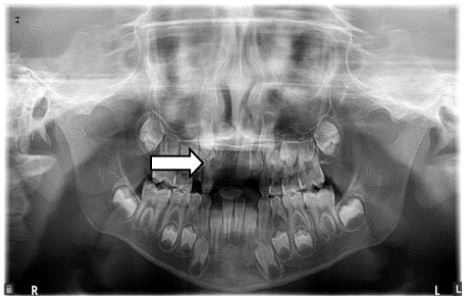

On radiographic investigation, IOPAR (Figure 3) and maxillary occlusal radiograph (Figure 4) revealed well defined radio-opacity superimposing normal radio density of right maxillary central incisor. In addition to above radiographic findings, OPG (Figure 5) also showed that the maxillary right lateral incisor was missing. After assessment of axial and coronal sections of CBCT of maxillary anterior region (Figure 6a, 6b, 6c. 6d, 6e), it was found that there was expansion and thinning of labial cortices of left maxillary central incisor. There was no radiographic evidence of root resorption of adjacent teeth. The root of right central incisor was dilacerated and curved with diffuse periapical rarefaction. At the area of maximum concavity, a well defined radio opaque mass was evident in the midline attached at CEJ of right maxillary central incisor (11) suggestive of odontome attached with the tooth. As a treatment plan, extraction of 11 along with the odontome was advised. After the surgery, the patient was called for follow-up and within a month, partial eruption of left maxiallary central incisor (21) was seen (Figures 8,9).

Figure 4: Maxillary occlusal radiograph shows Well defined radio opacity superimposing the radiodensity of tooth w.r.t.11, Occlusal surfaces of 53,54,55,16,63,64,65,26 are evident and well defined radio-opacity resembling the normal radiodensity of crown portion of 21,22,13,14.

Figure 5: OPG shows well defined radio opacity with cortical border superimposing the radiodensity of 11. Incomplete apex w.r.t. 21,16,26,36,46, Crown with 2/3rd root formation w.r.t. 22, Crown formation with 1/3rd root formation w.r.t. 13,23, Crown completeion w.r.t. 14,17,24,25,27,33,34,43,44, ½ of crown completeion w.r.t. 15,35,45,37,47 and Radiographically missing 12.